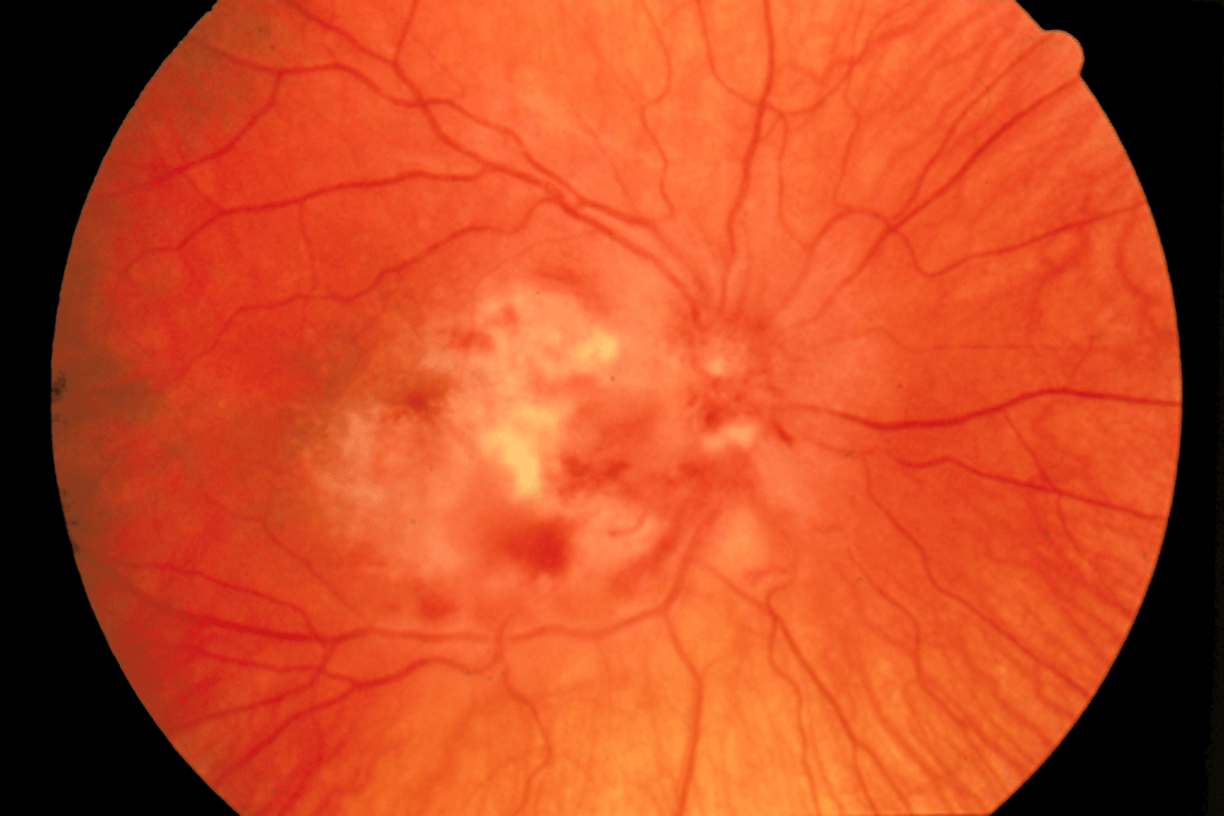

Under what CD4 count are HIV/AIDS patient at increased risk for CMV retinitis and what is the treatment?

CD4 <50

CMV retinitis is an AIDS defining illness

SSx: ↓ visual acuity, floaters/visual field cuts, photophobia.

Dx: Exam: white fluffy perivascular lesions with hemorrhage.

Tx: IV gancyclovir